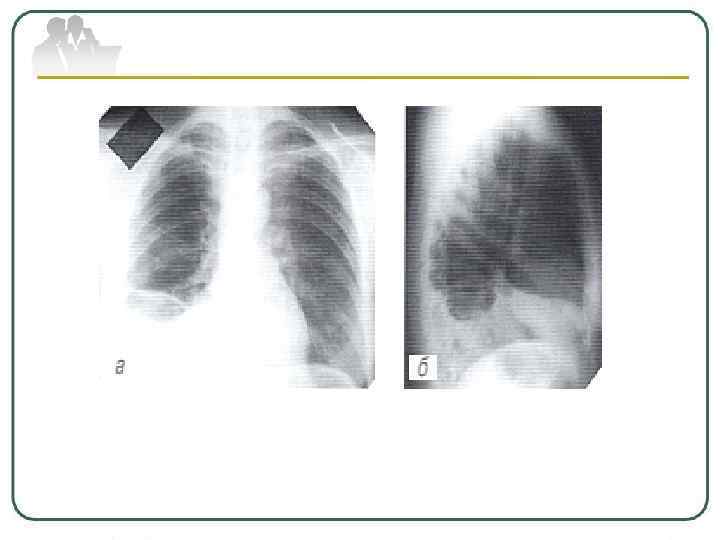

Туберкулез внутригрудных лимфатических узлов (ВГЛУ) развивается у детей, подростков и взрослых (18 - 25 лет) в результате первичного заражения туберкулезом. Реже возникает вследствие эндогенной реактивации имевшихся туберкулезных изменений во внутригрудных лимфатических узлах. Процесс эндогенной реактивации у взрослых характерен для больных с выраженным иммунодефицитом (например, у больных ВИЧ-инфекцией).

В случаях позднего выявления и неэффективного лечения возможен переход в хронически текущий первичный туберкулез, характеризующийся длительным волнообразным течением и полиморфизмом морфологических изменений в лимфатических узлах (кальцинированные, фиброзные, свежие воспалительные).

При всех вариантах туберкулеза ВГЛУ, но чаще всего при хроническом его течении, возможны осложнения в виде воспалительной реакции плевры, специфического поражения бронхов с развитием сегментарных или долевых ателектазов, диссеминации в легкие и различные органы (бронхолегочные формы процесса). Характерно возникновение различных клинических проявлений гиперсенсибилизации, описанных как "маски" хронического первичного туберкулеза (узловатая эритема, фликтены, полиартрит и др. ).